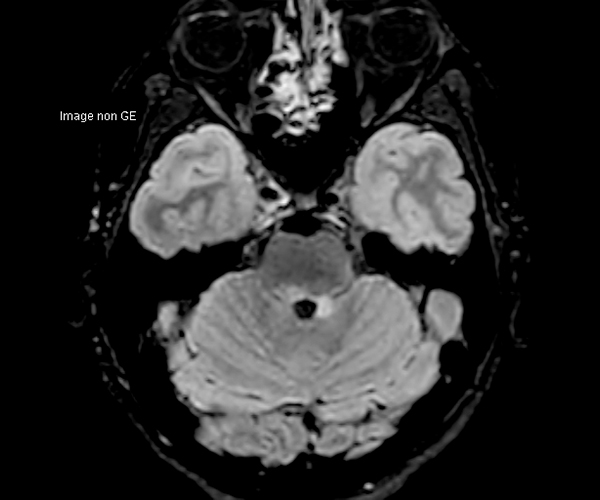

Concernant l’imagerie cérébrale, l’IRM 3T permet d’augmenter la sensibilité de détection de lésions ischémiques aiguës de petite taille, notamment chez les patients adressés pour accident ischémique transitoire (accident vasculaire cérébral), grâce à la séquence de diffusion dont le signal et la résolution sont augmentés.

L’amélioration de la résolution spatiale s’applique à l’exploration morphologique des hippocampes dans le diagnostic de la maladie d’Alzheimer, à la détection de petites lésions de sclérose en plaques ou de métastases, à l’étude fine du cortex dans les épilepsies.